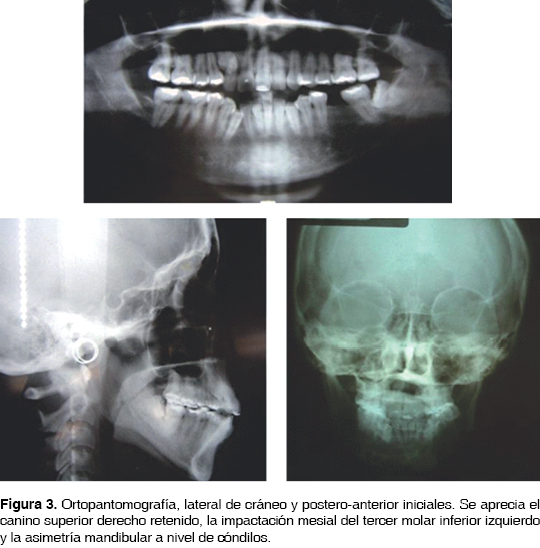

Solicitando atención en la Clínica de Ortodoncia de la División de Estudios de Postgrado e Investigación de la Facultad de Odontología de la UNAM, ingresa una paciente femenina de 29 años de edad, la cual refería estar ''preocupada por su canino retenido''. Se llevó a cabo la anamnesis, toma de modelos de estudio y radiografías extraorales (ortopantomografía, lateral de cráneo y posteroanterior). Como antecedentes, refirió una fractura de pelvis con intervención quirúrgica, así como la extracción indicada del primer molar inferior izquierdo por caries dental. El diagnóstico clínico reveló una paciente dolicofacial, de cara ovalada, perfil convexo, línea media facial no coincidente con la línea media dental superior, incompetencia labial, sonrisa gingival de 6 mm y una asimetría dentofacial moderada, con desviación mandibular hacia el lado izquierdo (Figuras 1 y 2). El diagnóstico cefalométrico indicó una clase II esquelética por retrognatismo moderado, biotipo dolicofacial, crecimiento vertical excesivo y biprotrusión dentaria. Al examen radiográfico se diagnosticó asimetría mandibular debido a elongación de la hemimandíbula derecha, principalmente a nivel de cóndilo y cuello condilar; se detectaron también las retenciones del canino superior derecho y del tercer molar inferior izquierdo; no existía un adecuado paralelismo radicular y había presencia de raíces cortas en múltiples órganos dentarios (Figura 3). Dentalmente presentaba clase III molar derecha, clase molar izquierda no valorable, clase canina derecha no valorable, clase II canina izquierda, leve mordida abierta anterior, mordida cruzada a nivel de premolares izquierdos, mordida cúspide a cúspide a nivel de segundos molares izquierdos, apiñamiento moderado superior e inferior, líneas medias dentales no coincidentes entre sí, canino inferior derecho con erupción ectópica y desgastes excesivos de las caras oclusales de los dientes posteriores. El análisis de modelos reveló colapsos maxilomandibulares tanto sagitales como transversales, confirmados al analizar la radiografía postero-anterior, la cual reveló que los anchos maxilar, mandibular e intermolar se encontraban disminuidos, y mostró una desviación de la línea media mandibular de 3.6 mm hacia la izquierda con respecto a la línea media maxilar, así como el plano oclusal canteado.